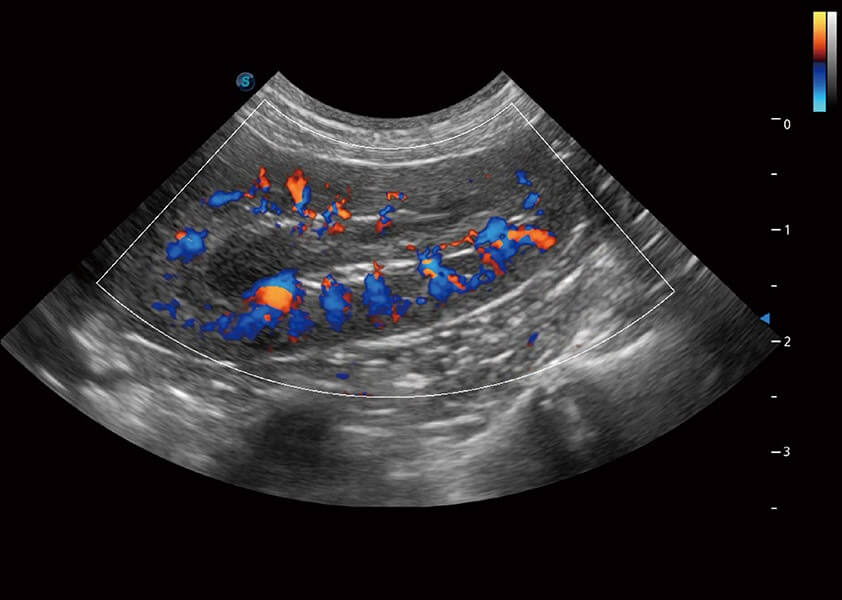

ProPet 60 作為一款高端臺式動物超聲設(shè)備,為動物醫(yī)生的日常診斷提供了一系列貼合動物臨床需求、解決臨床實際問題的高級成像功能。憑借全系列高清探頭,滿足醫(yī)生對腹部、心臟、生殖、淺表、肌骨等成像的所有需求,切實幫助您提升檢查效率,提高診斷信心。

獸用彩色多普勒超聲診斷系統(tǒng)